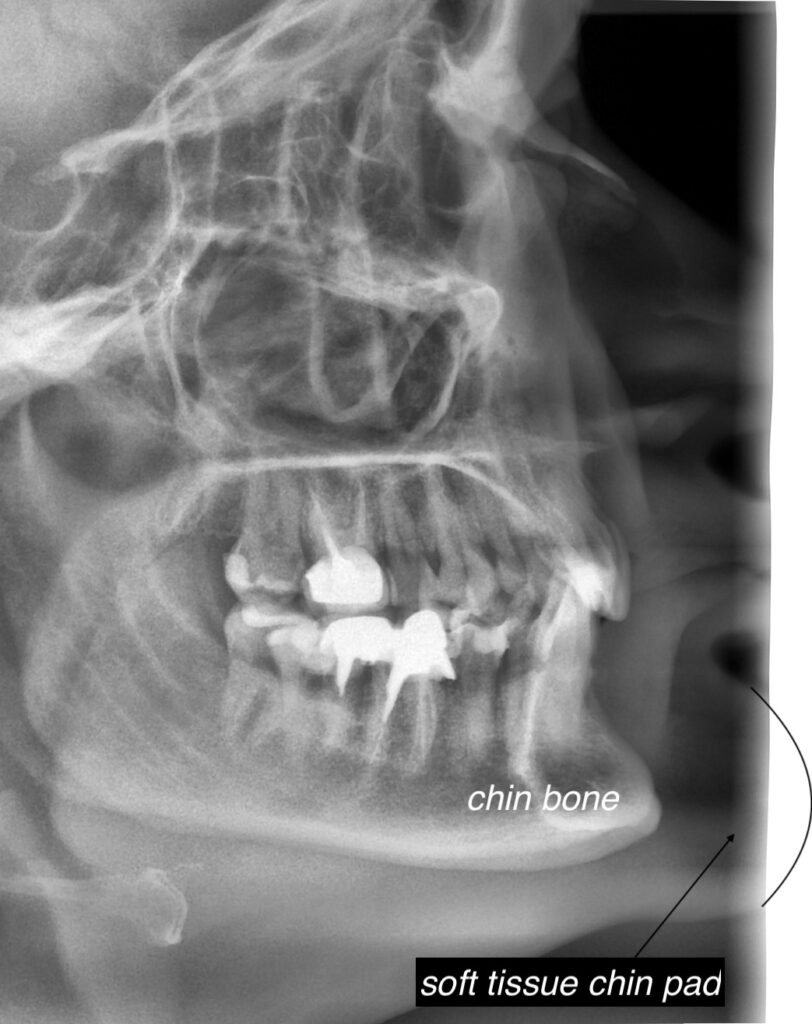

Chin Pad Reduction . If chin reduction is desired, three treatment options are available. It may involve techniques such. Limiting the length of the. Chin liposuction (aka submental liposuction) permanently removes excess fat from under the chin (the submental area) and jawline via small, thin tube called a. Soft tissue chin pad reduction can be done without bone reduction through a submental excisional approach. Genioplasty, also known as chin surgery or mentoplasty, is a type of cosmetic surgery that is done to change the shape of the chin. You have correctly surmised that submental soft tissue chin pad reduction with submental/neck liposuction would be a good. 2) soft tissue chin pad reduction, as mentioned above, can be effectively done through a submental approach. Kybella is a nonsurgical injection technique used to reduce excess fat beneath the chin. It uses a synthetic form of. After removal of skin and underlying fat, the. Each treatment takes about 15 to 20 minutes.